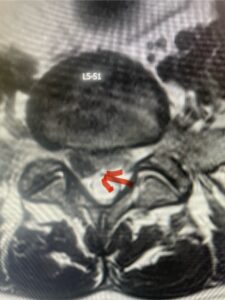

This 61-year-old female with a history of severe osteoporosis and a prior history of a laminectomy from l2-S1 with an L5-S1 instrumented fusion, presents with progressive low back pain and right lower extremity radiculopathy. MRI revealed a grade 1 L2-3 spondylolisthesis with severe stenosis mainly from severe right L2-3 facet joint hypertrophy which was compressing the right L3 descending nerve root. (Fig. 1). She had failed conservative management consisting of physical therapy and pain management with epidurals. She underwent an L1-3 revision laminectomy where we had to dissect a plane underneath the inferior aspect of the L2 lamina. We performed an instrumented fusion at L2-3 with special hydroxyapatite-coated screws to improve fixation to surrounding bone given here severe osteoporosis (Fig. 2) This worked out well and the patient had an uneventful recovery with relief of her leg pain.

Figures 1a: Sagittal and axial T2-weighted lumbar MRIs demonstrating a grade 1 L2-3 spondylolisthesis (red arrow) with severe stenosis secondary to right L2-3 facet hypertrophy (red arrow).

Fig 1b: Note the left L2-3 facet joint (blue arrow) is normal in size compared to the right (red arrow)